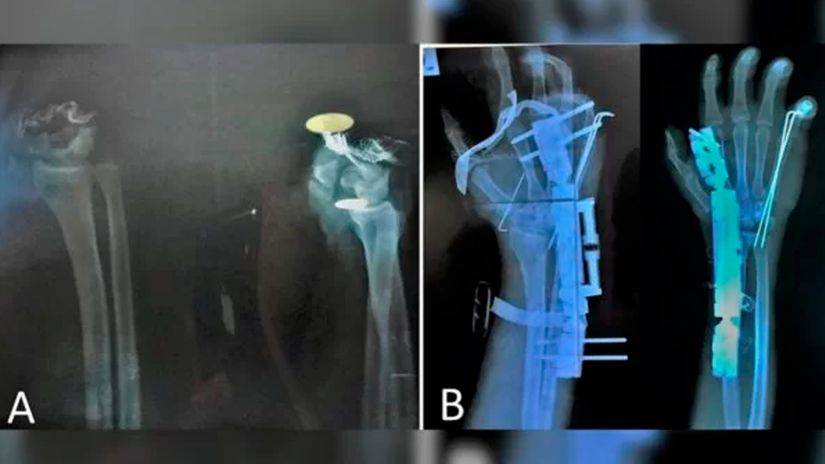

Depois de ter a mão decepada com um cutelo por assaltantes, um rapaz de 20 anos na Síria foi levado rapidamente à emergência de um hospital e, após 10 horas de cirurgia, os médicos conseguiram reimplantar o membro.

O caso foi relatado na revista científica International Journal of Surgery Case Reports em 11 de agosto. Os médicos do hospital Al-Razi contam que o paciente foi levado ao pronto-socorro uma hora depois de ter a mão esquerda cortada. Ela estava envolvida em um pano.

A cirurgia de reimplante foi realizada com anestesia geral e durou 10 horas. “É um procedimento complexo, que exige equipe médica multidisciplinar e equipamentos adequados para a microcirurgia”, aponta a equipe. Eles explicaram ainda que a operação só foi possível pela rapidez com que o rapaz procurou ajuda médica.

O objetivo da cirurgia era reintegrar o jovem à sociedade com as habilidades da mão plenamente restauradas, “o que foi quase bem-sucedido”. O paciente recebeu alta hospitalar sete dias após a operação e foi acompanhado regularmente por dois anos e sete meses.